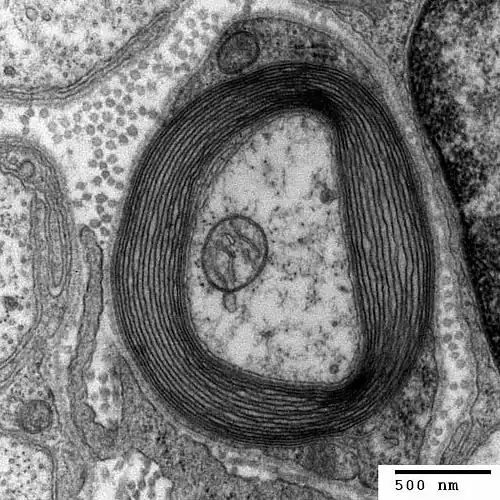

Fast-transmitting axons (especially those running from the feet to the head) are surrounded by myelin. These are insulating cells, like an insulating wall on an electrical wire. They reduce the capacity of an axon wall, because they increase its thickness, and thus accelerate the propagation of the nerve impulse, because thanks to them, it takes less time to discharge the membrane. Myelin is made of cells that wrap around an axon:

The axon is in the center. Its wall is thickened by a myelin cell (a Schwann cell) which has wrapped around the axon.

The insulating myelin wall is interrupted at the nodes of Ranvier to allow the flow of ion currents which charge the axon (the ion pumps) or discharge it (the signal transmission relays):